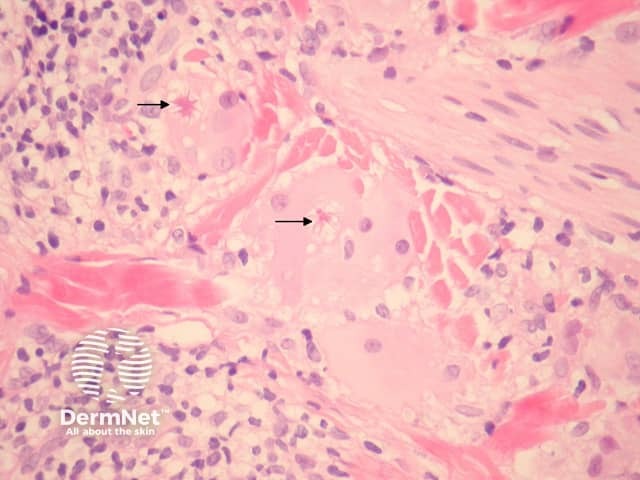

Sections show a granulomatous and lymphocytic infiltrate involving the dermis (figures 1, 3). The giant cells often contain asteroid bodies (figure 2, arrows). There is an associated infiltrate containing histiocytes, lymphocytes and some plasma cells (figures 1, 2).

Figure 2